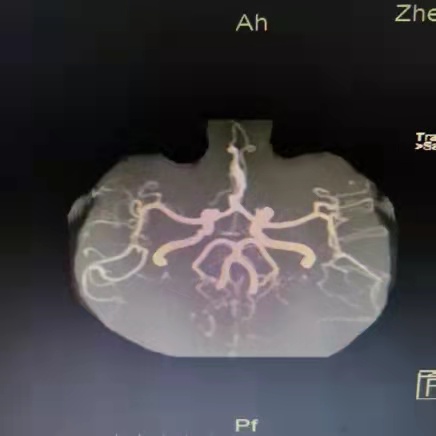

病例2 患者为男性,22岁,在全麻状态下进行手术。术后,患者出现左侧肢体无力、反应迟钝、记忆力下降,来到郑州大学第二附属医院就诊。头颅磁共振检查结果提示:右侧额顶叶大面积脑梗死,双侧颈内动脉末端重度狭窄及闭塞。脑动脉造影检查结果提示烟雾病。若有此病,患者在儿童时期即可出现脑梗死,有偏瘫、肢体麻木、复视等表现;成年后,还易发生脑出血,给患者及家庭带来极大痛苦和负担。对于此病,早期发现,可进行血管重建手术,恢复脑血流,避免后期发生卒中的风险。